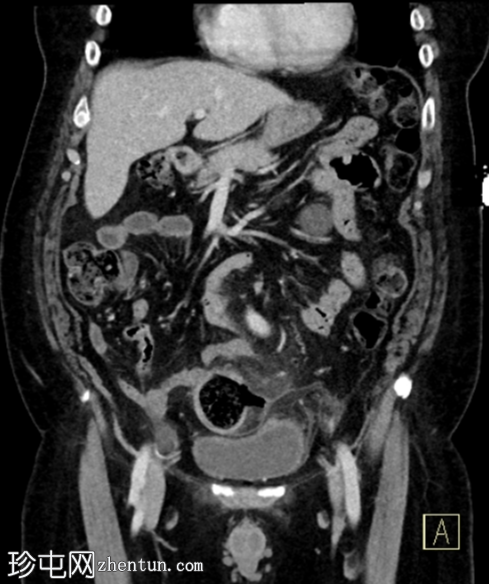

冠状位增强扫描(门静脉期)

2.png

多发性乙状结肠憩室。

乙状结肠壁增厚,伴结肠周围脂肪条索影,左侧壁局部穿孔。未见肠外脓肿、腹水或气腹,提示IA期复杂性急性憩室炎。

脂肪肝。

胆囊切除术夹。

双侧肾盂周围及皮质囊肿,左侧较大。